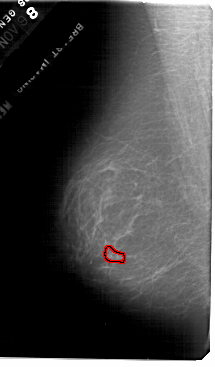

A_1872_1.LEFT_MLO

FILE: A_1872_1.LEFT_MLO.OVERLAY

TOTAL_ABNORMALITIES 1

ABNORMALITY 1

LESION_TYPE CALCIFICATION TYPE PLEOMORPHIC DISTRIBUTION CLUSTERED

ASSESSMENT 4

SUBTLETY 1

PATHOLOGY MALIGNANT

TOTAL_OUTLINES 1

BOUNDARY